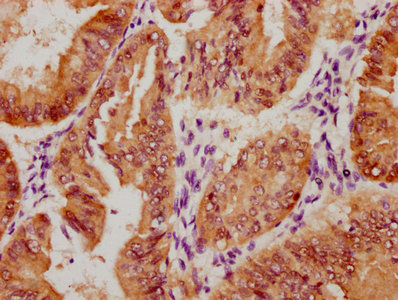

The image on the left is immunohistochemistry of paraffin-embedded Human thyroid cancer tissue using CSB-PA985822(ATP2A3 Antibody) at dilution 1/30, on the right is treated with synthetic peptide. (Original magnification: ×200)